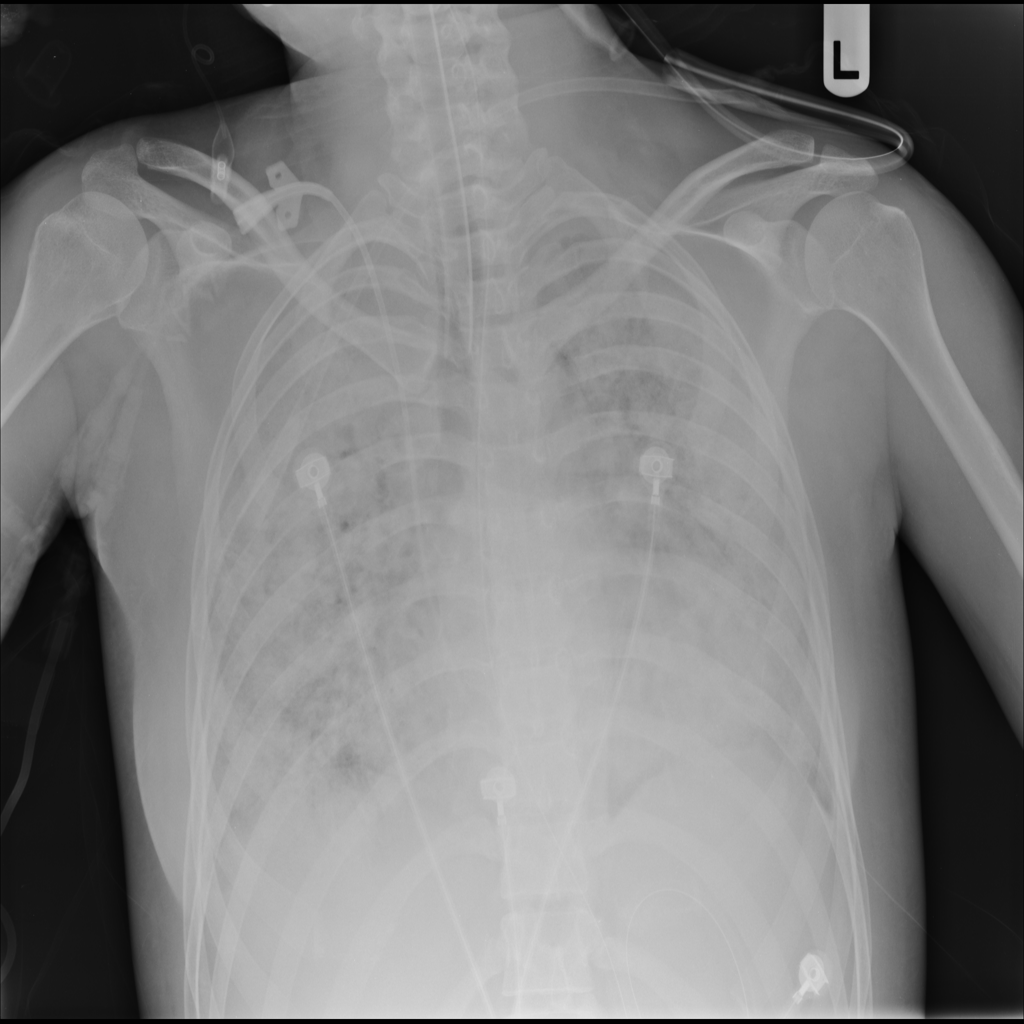

PAT-531A · IMG-006Consolidation

PAT-531A · IMG-006

PA